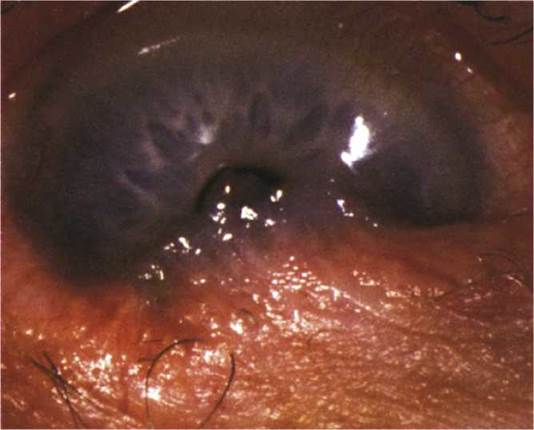

FIGURE 5.7.1 Nodular scleritis.

FIGURE 5.7.2 Necrotizing scleritis with thin, bluish sclera.

2. Nodular anterior scleritis: Immovable inflamed nodule(s) (see Figure 5.7.1).

3. Necrotizing anterior scleritis with inflammation (see Figure 5.7.2): Extreme pain. The sclera becomes transparent (choroidal pigment visible) because of necrosis. High association with systemic inflammatory diseases.